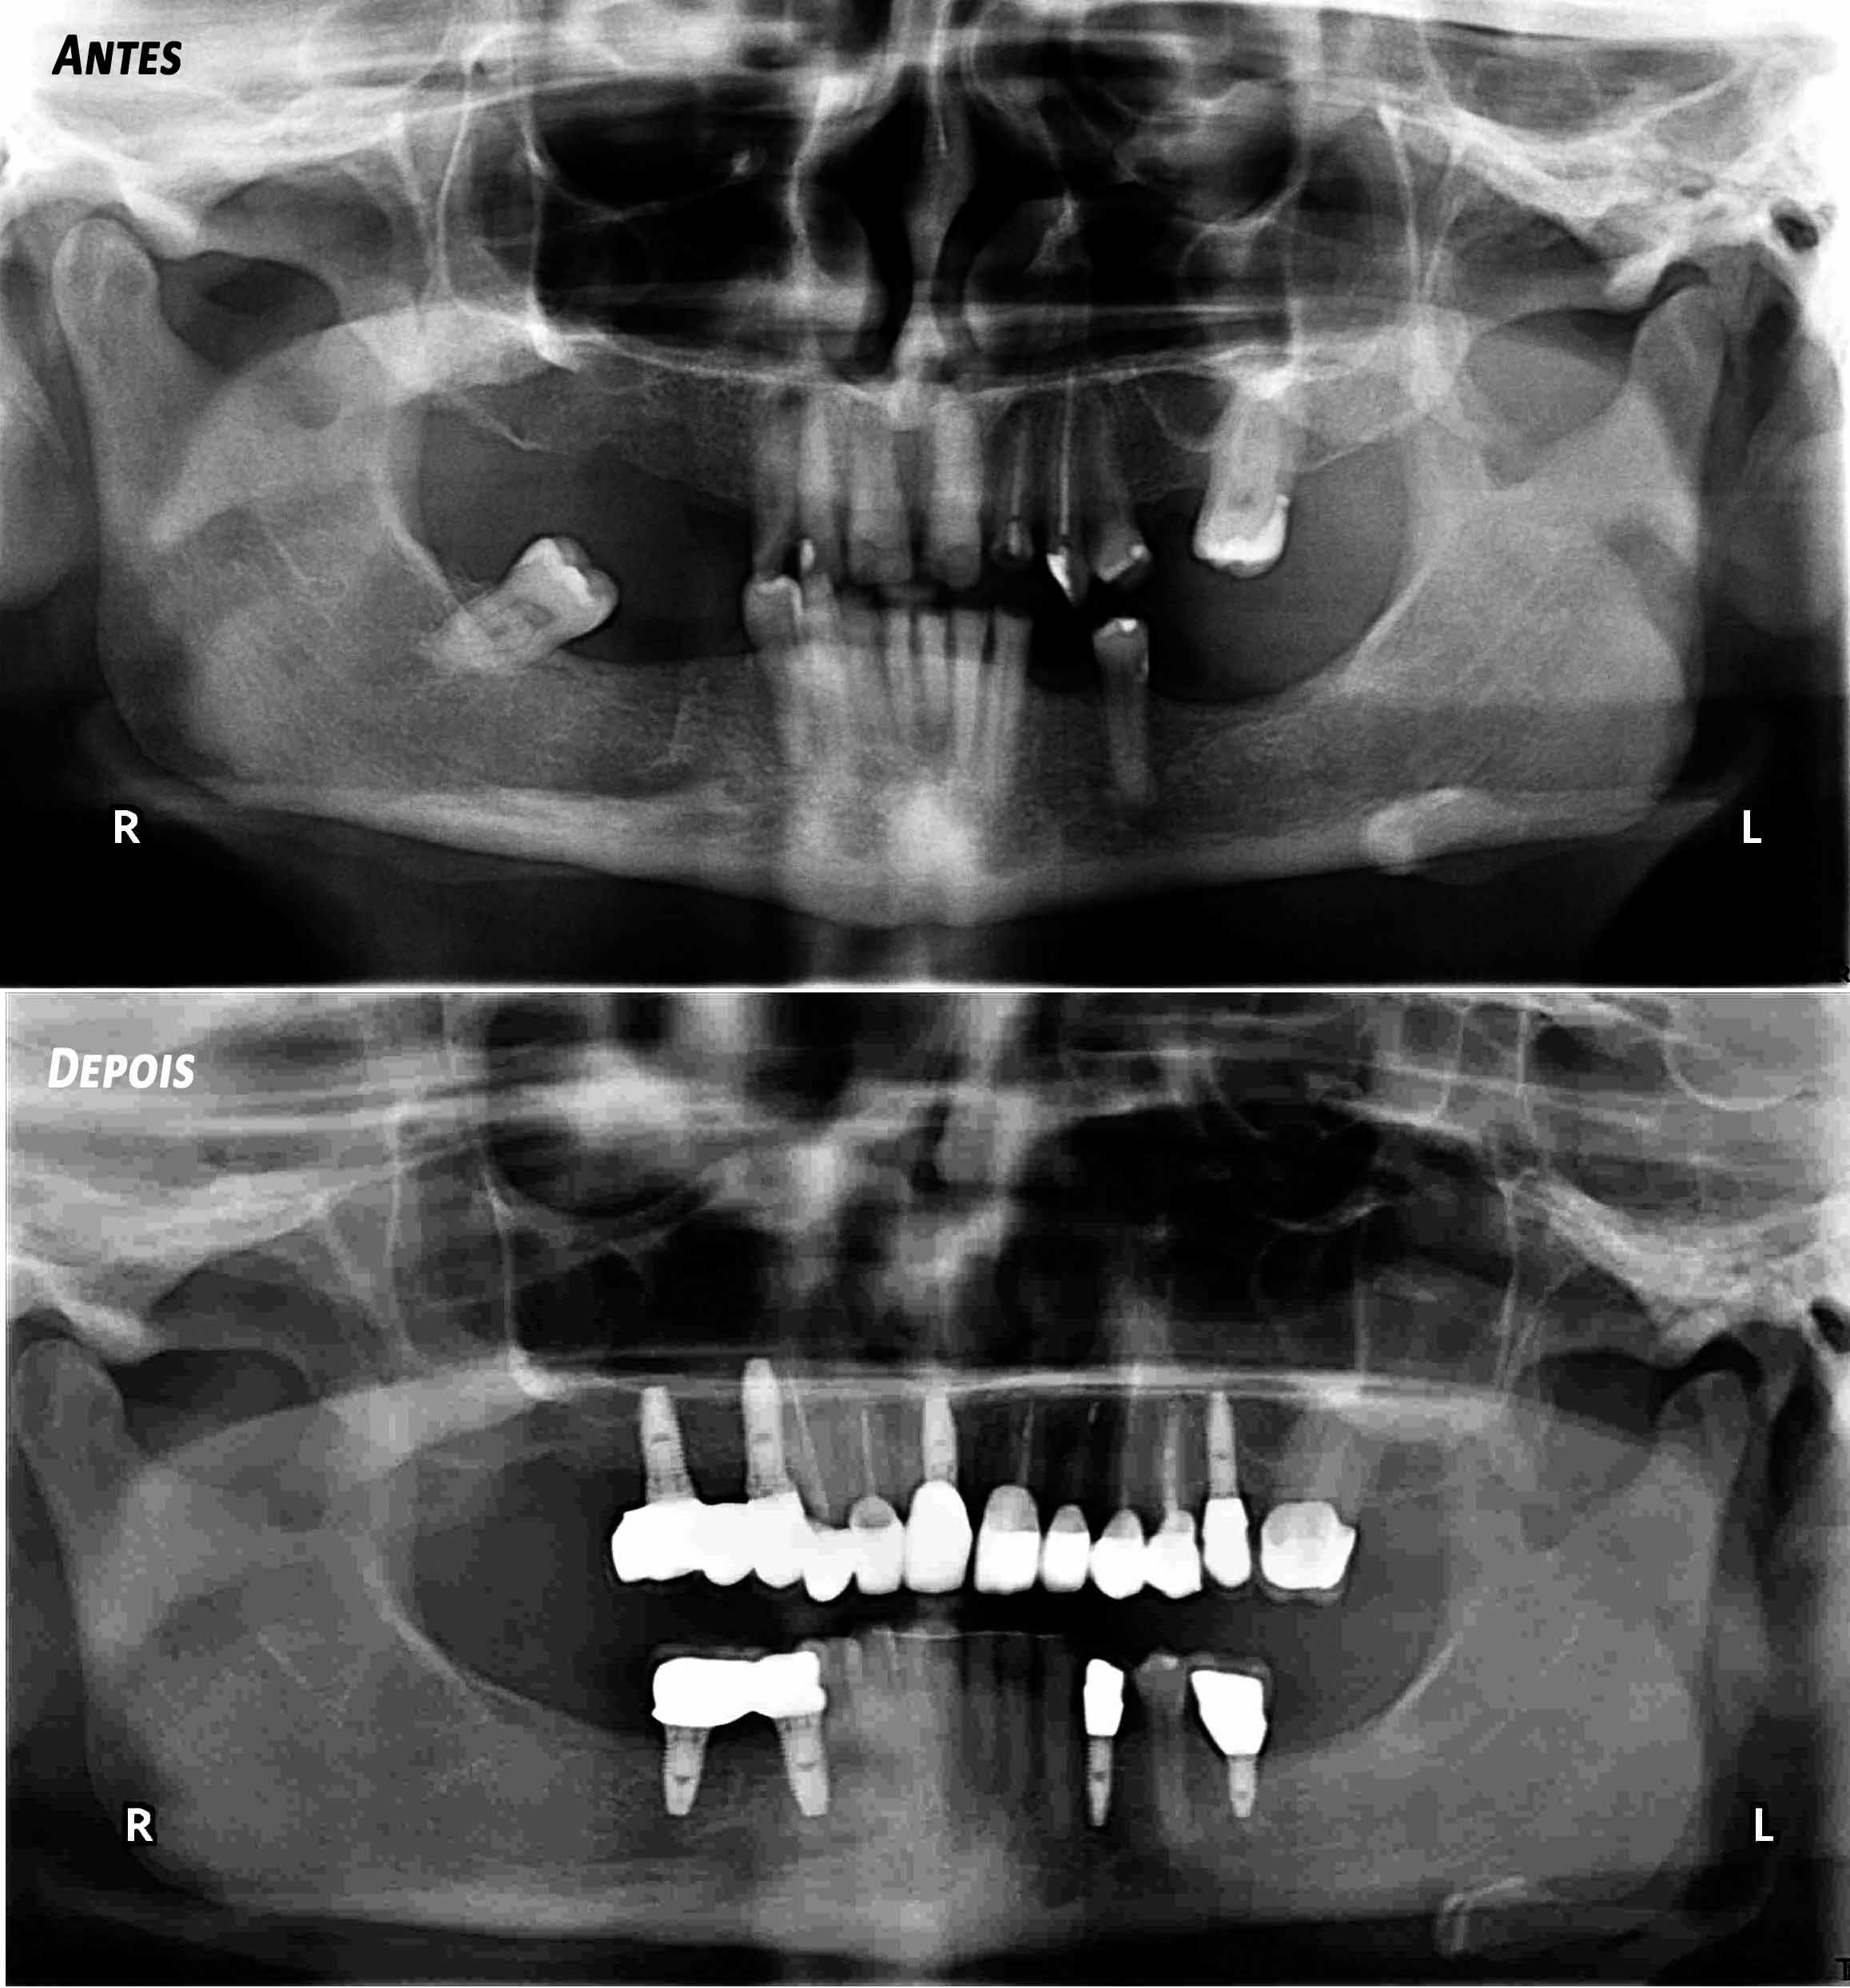

Complex Rehabilitation – The Treatment:

The natural teeth that had a good prognosis were kept and the ones that needed their position changed were moved by a fixed orthodontic brace.

Afterward a surgery was made to place some implants. The treatment was finalized by placing the ceramic crowns over the implants and teeth.